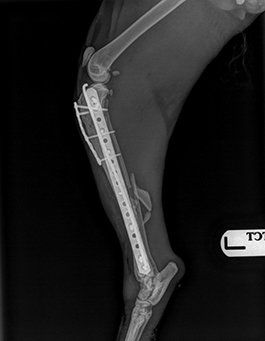

Whether it be a serious fracture, a luxating patella, a cruciate rupture, or serious joint damage, then this service can help your pet , or your patient.

Working alongside the vets and nurses who know your pet so well, I can add my expertise and experience to their on going care.